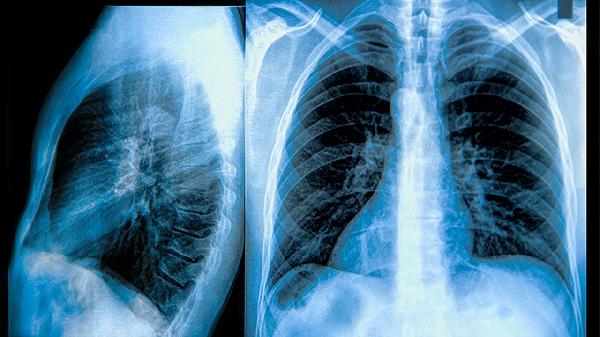

肺部不张可通过体位引流、呼吸训练、药物治疗、支气管镜治疗、手术治疗等方式改善。肺部不张可能与痰液阻塞、肿瘤压迫、感染、胸膜疾病、外伤等因素有关,通常表现为呼吸困难、咳嗽、胸痛等症状。